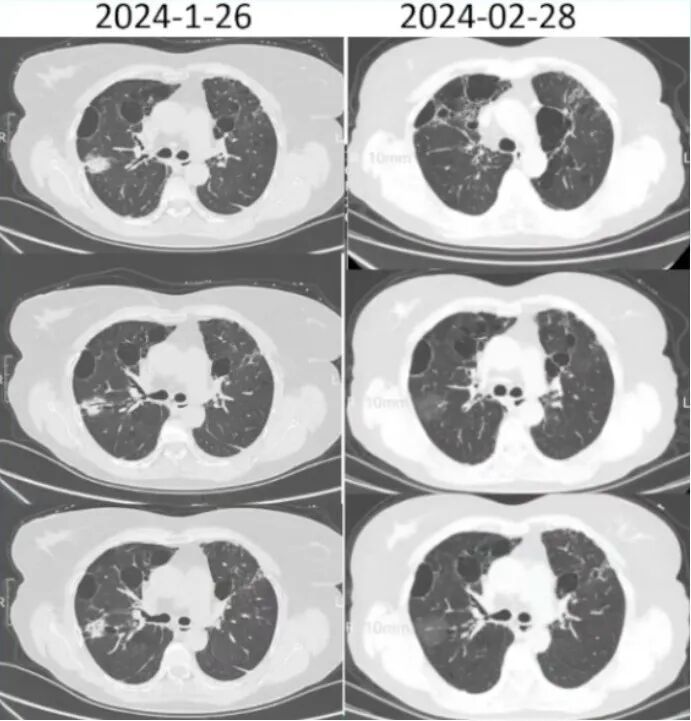

9. 胸部CT2024-01-26

胸廓基本对称,双肺内示片状及网格样高密度影116片未见明显改变,各主支气管开口通畅,双肺内散在低密度影纵隔内未见明显肿大淋巴结(图2)

【出院后1个月】2024年2月28日,查CRP 34.42 mg/L。胸部CT(图3):胸廓基本对称,双肺内片见状及网格样高密度影,右肺部分病变较前密度减低,各主支气管开口通畅,双肺内示散在低密度影;纵隔内未见明显肿大淋巴结,前纵隔内示约0.9 cm×0.5 cm结节影,边界清晰,密度均匀。

图片

【出院后2个月】2024年3月27日,CRP 2.04 mg/L。胸部CT(图4):胸廓基本对称,双肺网格样高密度影,双肺内散在低密度影;各主支气管开口通畅,纵隔内未见明显肿大淋巴结,前纵隔内示约0.9 cm×0.5 cm结节影,边界清晰,密度均匀。嘱继续口服艾沙康唑治疗。

【出院4个月】2024年5月22日常规随诊,复查血常规,CRP 15.86 mg/L,其余无异常。胸部CT(图5):考虑双肺间质纤维化可能性大;肺气肿,肺大疱;双肺小结节;前纵隔结节;双侧胸膜增厚。患者艾沙康唑已服用4个月,肺部病灶吸收可,暂停用观察半月,如有不适,及时复查,3个复查胸部CT。

5  患者胸部CT变化